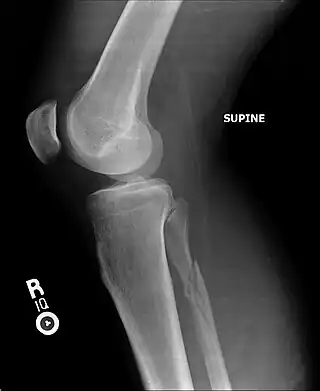

![]() Radiografía de una fractura de peroné | ||